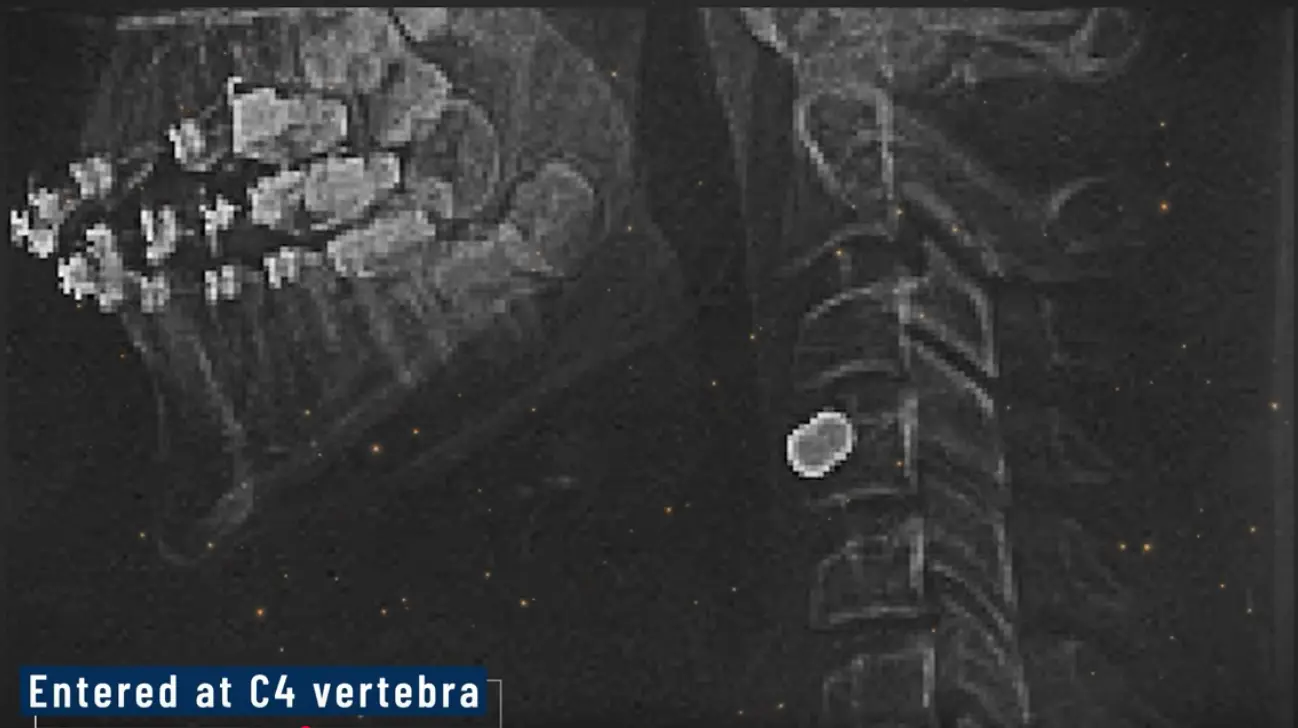

Shortly after the incident, I got this photo off the web which was supposed to be an x-ray of Kirk showing the bullet in him.

Screen Shot 2025-09-17 at 8.59.15 AM.webp